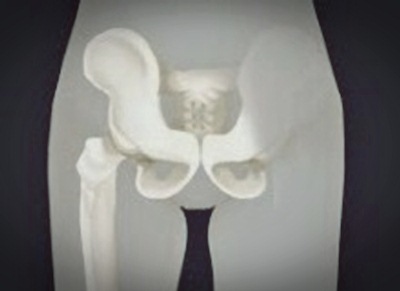

고관절은 우리몸의 187개 관절 중 하나로, 사람에서 가장 큰 관절 중 하나이다. 체중의 1.5에서 최대 10배의 하중을 지탱해주는 역할을 하며 척추와 함께 우리 몸의 기둥 역할을 한다.

고관절의 구조를 보면 재미있는 부분이 있다. 대퇴골두라 불리는 공처럼 둥근 넓적다리뼈의 머리 부분과 이 부분을 감싸는 절구 모양으로 생긴 골반골인 비연구골로 구성되어 있다. 주로 앞뒤로 움직이는 무릎관절과 다르게 고관절의 움직임은 앞뒤, 좌우, 회전 등 움직임의 범위가 넓은 것이 특징이다.

이처럼 골반과 다리를 연결해주며, 체중 지탱과 함께 보행을 돕는 핵심적인 역할을 하기 때문에 그 구조가 안정적이다. 이런 안정적인 구조에도 불구하고 고관절 건강을 챙기지 않으면 고관절 충돌 증후군 등 관절 질환을 호소할 수 있다.